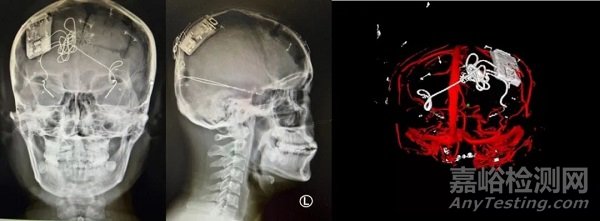

本次手術(shù)過程順利,術(shù)中刺激器各項(xiàng)指標(biāo)均工作正常,術(shù)后重建顯示電極位置精準(zhǔn),腦電信號清晰。患者為男性,入院后診斷為雙側(cè)顳葉癲癇,此類癲癇為開顱手術(shù)的相對禁忌癥,在藥物無法控制的情況下,傳統(tǒng)治療效果欠佳 。

團(tuán)隊(duì)根據(jù)術(shù)前計(jì)劃,在手術(shù)機(jī)器人輔助下完成雙海馬長軸電極及 IPG 植入,術(shù)后重建顯示電極位置精準(zhǔn),腦電信號清晰。術(shù)后第二天,患者即下床活動(dòng),身體狀況恢復(fù)良好。